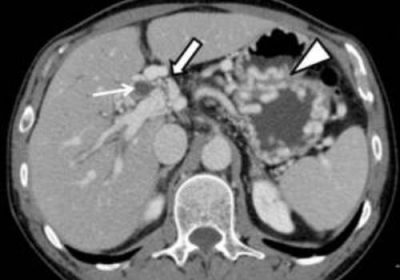

Также для диагностики патологии специалисты прибегают к флебографии. Данный метод используется в тех случаях, если предыдущие два метода не дали точных сведений и вызывают сомнения. При этом подобное исследование подразумевает введение в вену контрастного вещества, который представляет собой краситель просвечиваемый рентгеном. В результате на снимке четко обозначены места в сосудах, где сгусток блокирует кровоток.